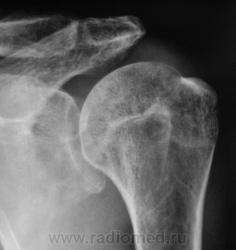

Снимок "без обрезания" - ниже. Врача-рентгенолога в кабинете не было, лаборанты, оценив его, начали "пытать" пациента. Оказалось, что флюорографию органов грудной полости, этот пациент, "проходил" лет 5 тому. Ну, и лаборанты приступили к стандартному исследованию органов грудной полости.

Лаборанты проводили исследование согласно стандарту, хорошие лаборанты, а это значит, что рентгенологически пациент будет "добит", и будет передан по назначению, даже без врача-рентгенолога. Когда я появился в кабинет исследование было закончено.

Рентгенограммы в стандартных проекциях - прямая и боковая.

При таких загонщиках этот махровый рак лёгкого – "лёгкая добыча рентгенолога". Со всей его свитой.

Вы правы Петрович!